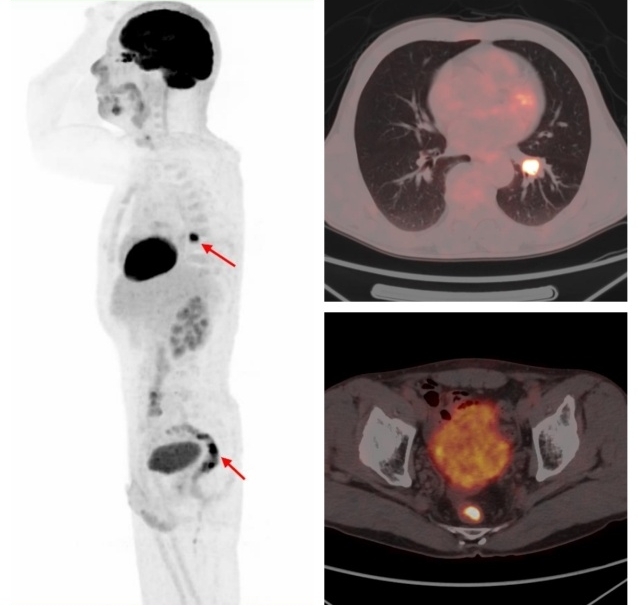

國際頂級腫瘤期刊《美國醫(yī)學(xué)會雜志腫瘤學(xué)(JAMA Oncology)》的數(shù)據(jù)顯示,65歲以上的老年癌癥患者二次患癌的概率為25.2% 。多原發(fā)癌好發(fā)于消化系統(tǒng)、呼吸系統(tǒng)和泌尿系統(tǒng)。有研究發(fā)現(xiàn)FDG PET/CT在3%的非小細(xì)胞肺癌患者中發(fā)現(xiàn)了第二原發(fā)性惡性腫瘤或癌前病變,從而改變了27%的患者的治療方案。

原發(fā)肺鱗癌合并直腸腺癌